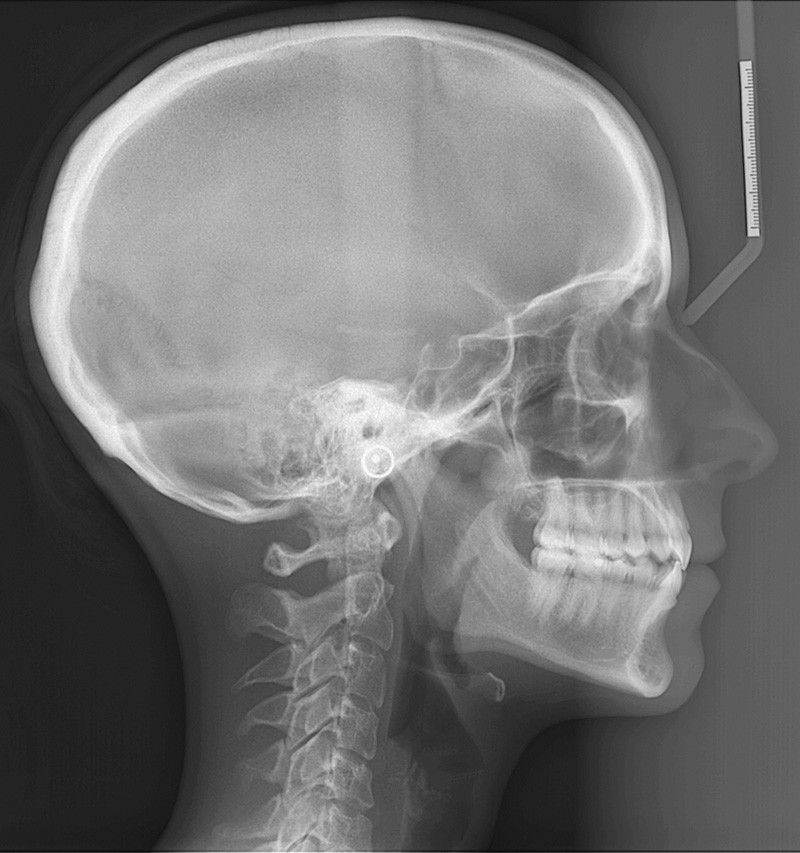

L’examen de la téléradiographie de profil fait apparaître un schéma squelettique normodivergent de classe I (fig. 8).